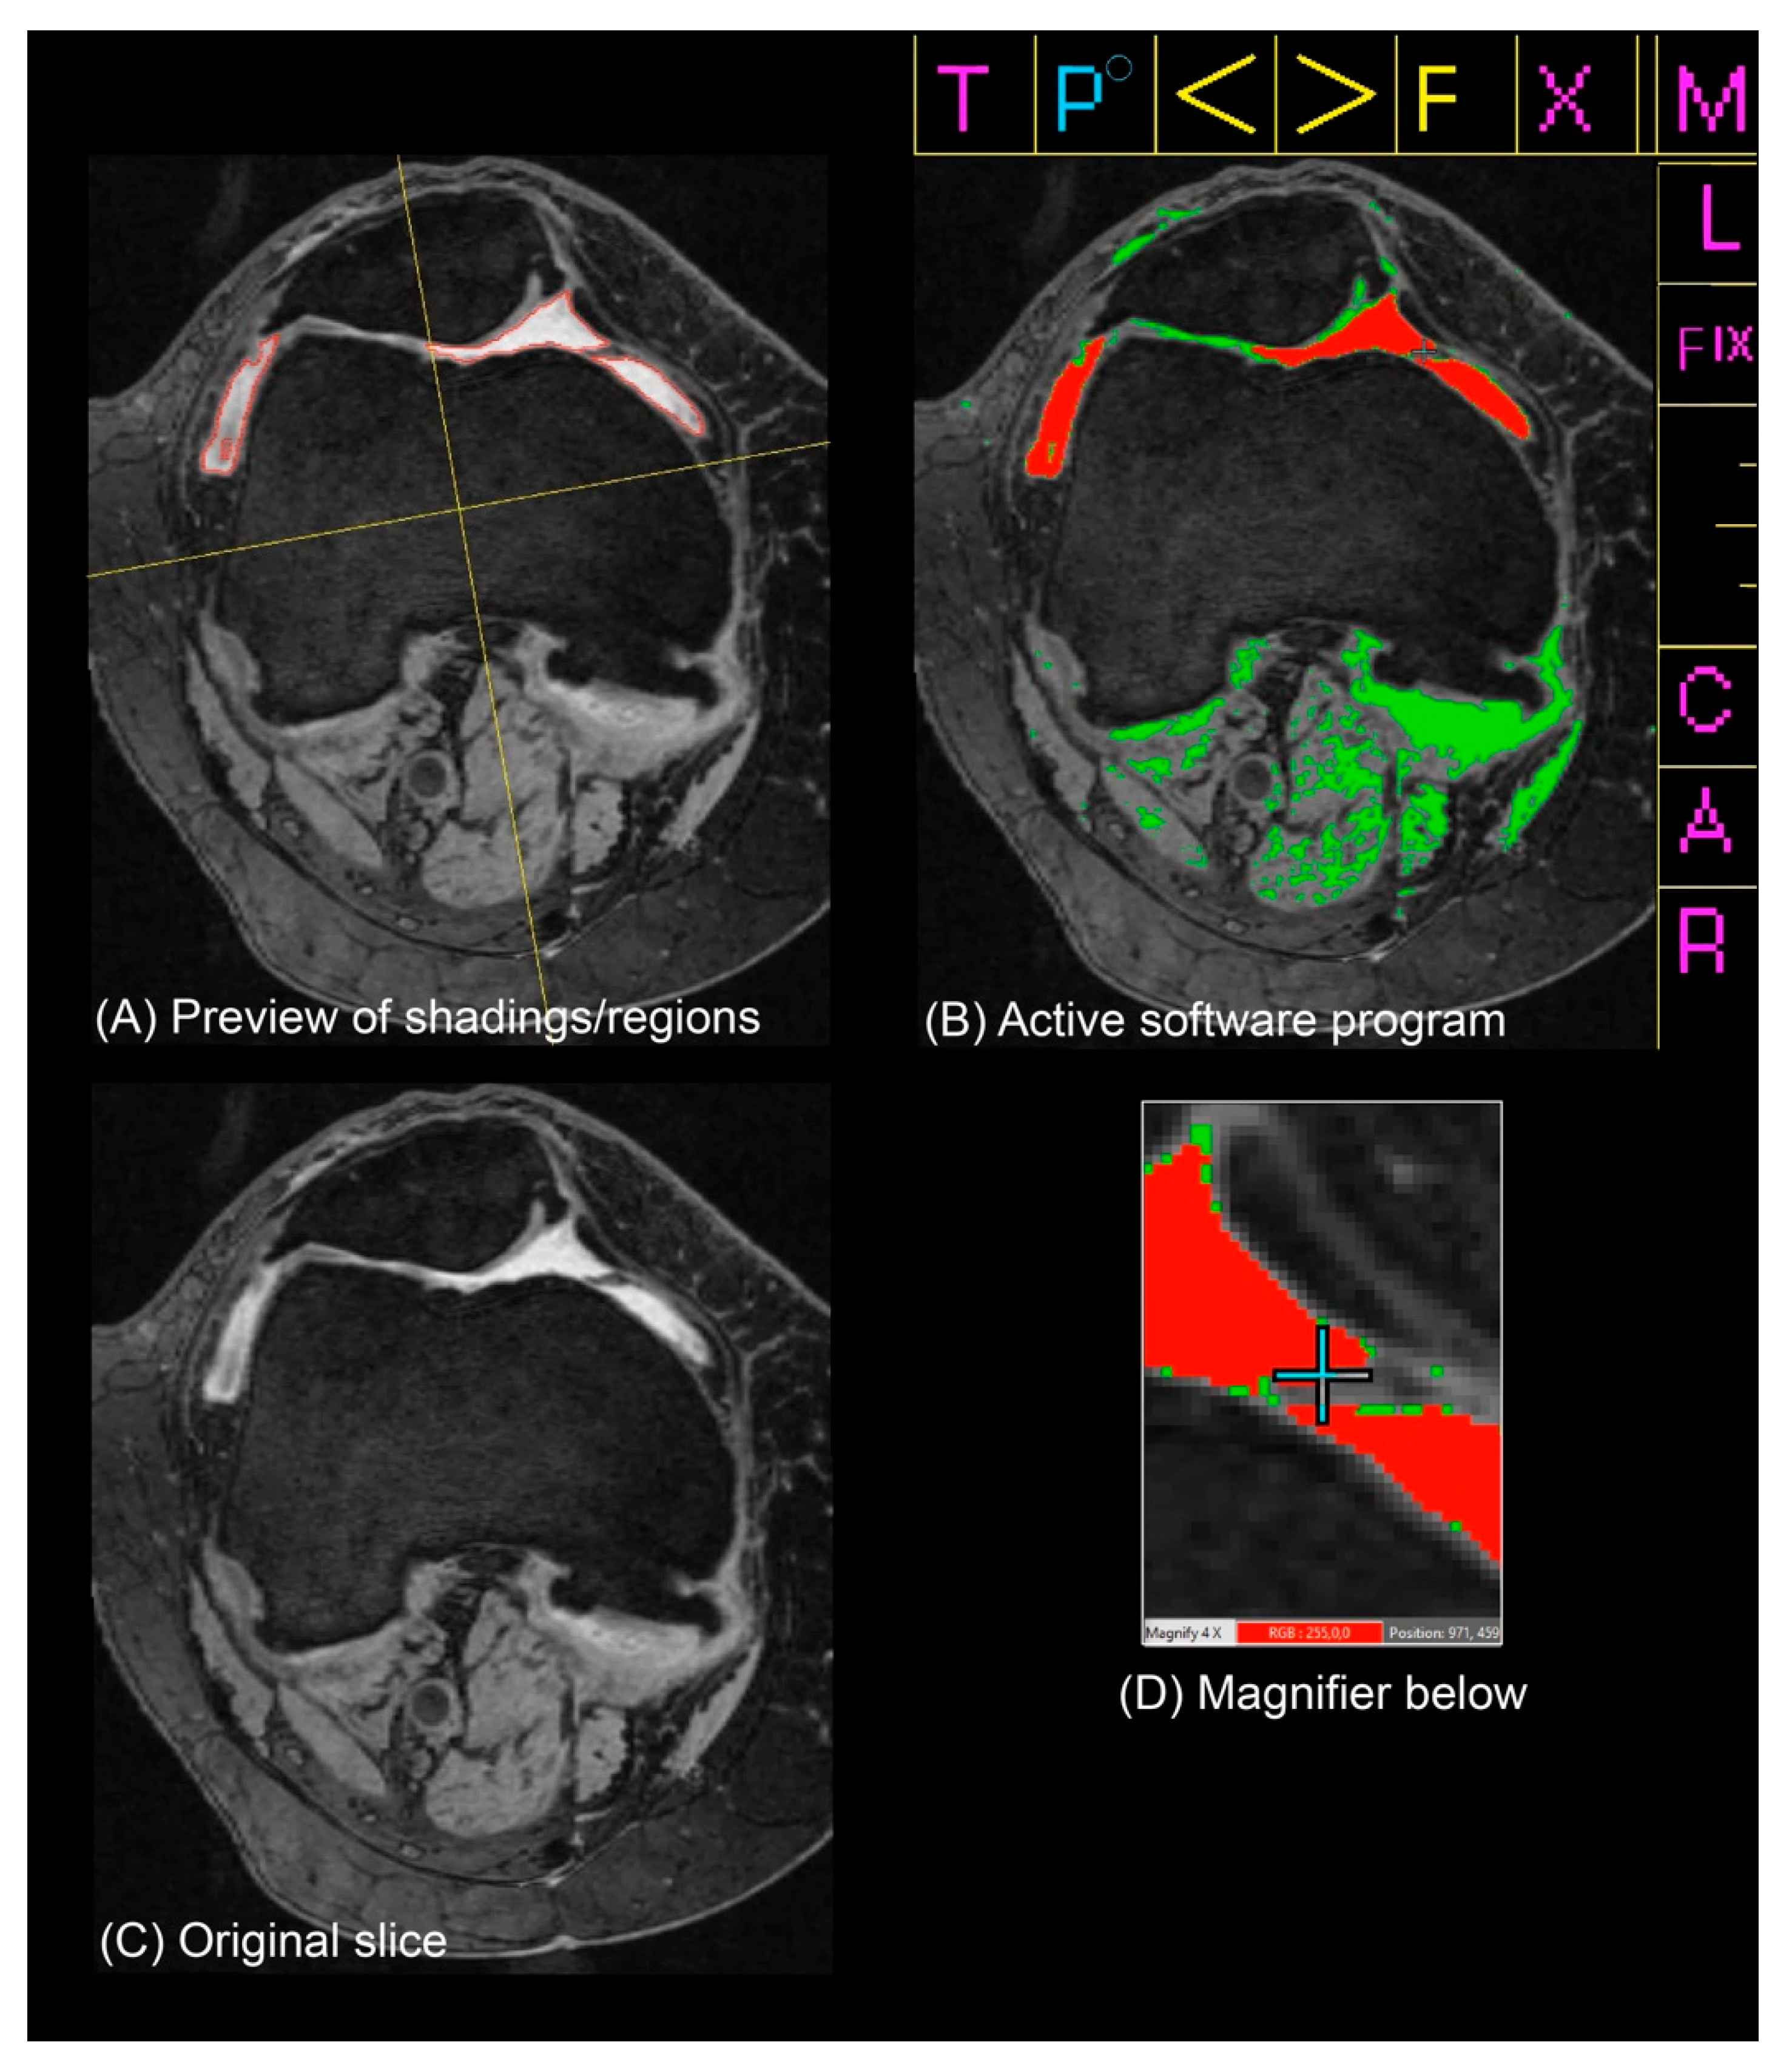

2.4. Semi-Automated Quantitative Assessment of Effusion-Synovitis